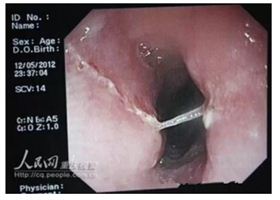

10.多刺的魚